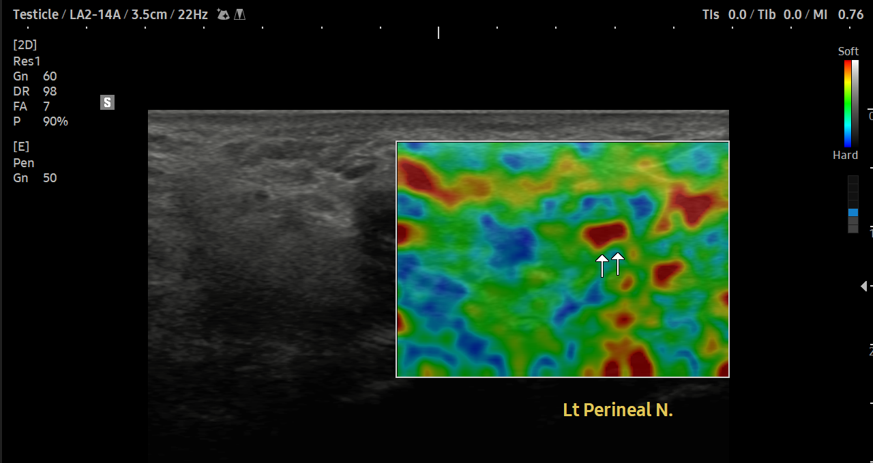

- 치료기간 : 25 . 8 .19 ~ 25 . 11 . 20

- 치료횟수 : 25 회 (사이클 치료 3 +아피톡신 10회)

치료 전

치료 후